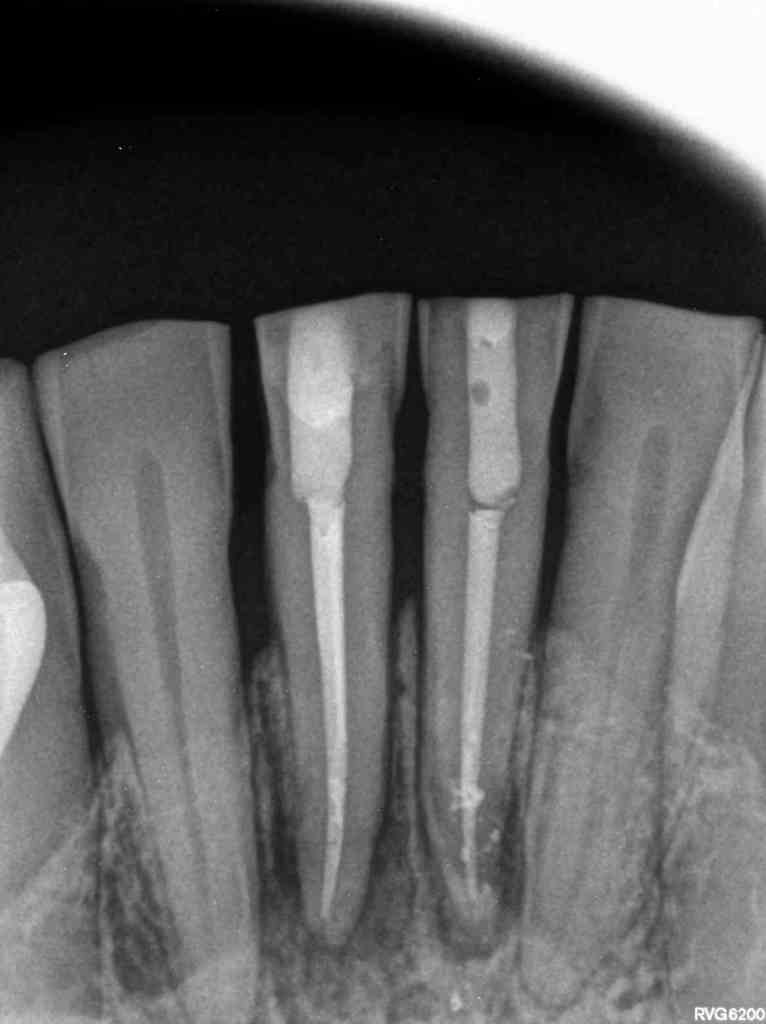

El paciente acude a la consulta en 2022 con sintomatología compatible con necrosis pulpar en el diente 3.1. Tras la confirmación diagnóstica, se realiza el tratamiento de conductos. Un año después, el diente 4.1 presenta un cuadro clínico similar, asociado a la sobrecarga funcional derivada del bruxismo. Se diagnostica necrosis pulpar y se procede igualmente a realizar tratamiento endodóntico. En 2025, el paciente acude con la presencia de una fístula vestibular a nivel del 4.1. Tras la evaluación clínica y radiográfica, se concluye la existencia de una fractura radicular vertical, lo que compromete el pronóstico del diente (Figuras 1-6).